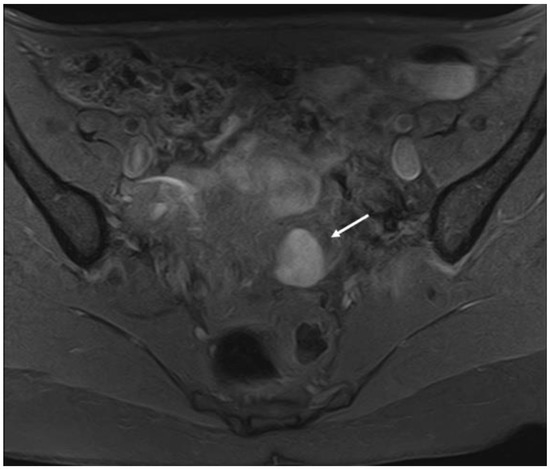

3.1. Ovarian Endometriosis

3.3. Deep Endometriosis